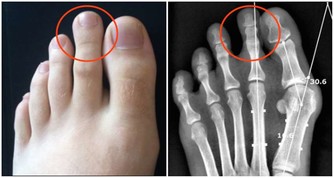

線索六:內八字

預警:風濕性關節炎

這種炎症會造成內八字的步態,有85%的風濕性關節炎患者會表現出這種特徵。它在醫學上被稱為膝外翻或者外翻足,表現為小腿無法伸直,向外側彎曲。這種步態非常與眾不同,看上去笨拙,雙膝併攏在一起,而踝關節外翻。